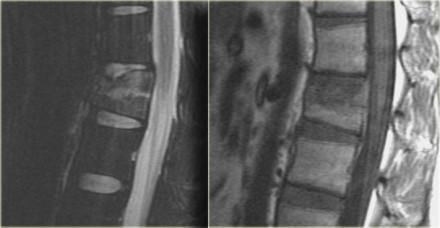

In this case it is clear that we are looking at an unstable fracture, because this is a burst fracture.

Both the anterior and the middle column are disrupted.

In addition there is edema in the posterior soft tissues indicating that there is also involvement of the posterior column.

Notice also the marrow edema in the adjacent bodies due to the severe axial loading.